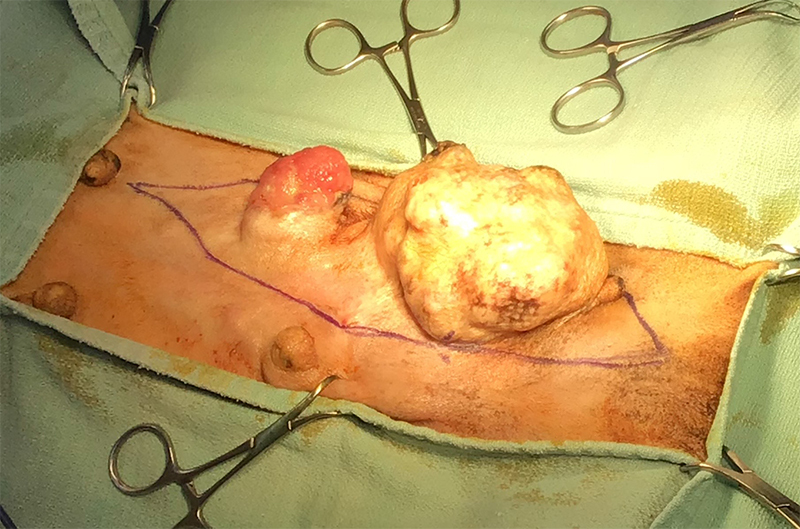

-

手術前(肝臓腫瘍で腹部が張っている) -

摘出した大型の肝臓腫瘍 -

手術後(腹部が正常になる)